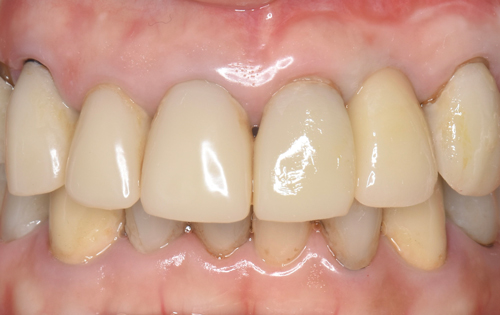

患者様はインプラントを選択され、抜歯から10ヶ月後の今月、無事にインプラントがセットされました。

クリスマス前に届いた綺麗に仕上がった前歯をセット致しました。完璧な仕上がりに、とても喜んで下さいました。